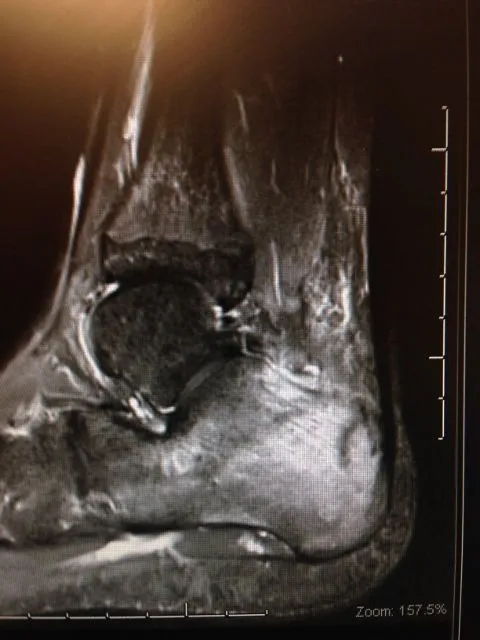

MRI imaging is excellent for diagnosing stress fractures. A T1 weighted image will show normal bone in a white color and edema and/or fracture lines in gray to black color (below left). T2 weighted imaged are the opposite and will show bone black and any fluid like swelling within the bone or throught a fracture as white (below right).